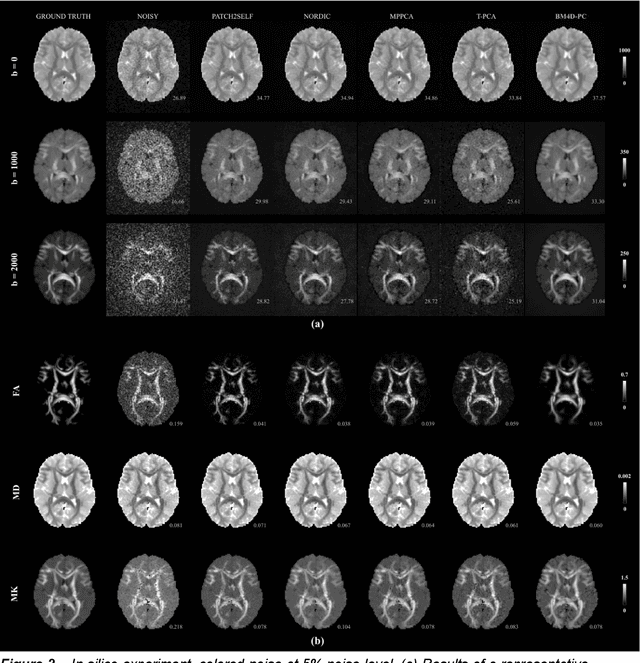

Abstract:Purpose: Noise in diffusion-weighted MRI (dMRI) is often spatially correlated due to different acquisition and reconstruction strategies, which is not fully accounted for in current denoising strategies. Thus, we propose a novel model-based denoising method for dMRI that effectively accounts for the different noise characteristics of data. Methods: We propose a denoising strategy that incorporates full noise statistics, including the noise power spectral density (PSD), by leveraging the BM4D algorithm. Furthermore, to exploit redundancy across the diffusion MRI dataset, BM4D is applied to principal components (PC) of diffusion-weighted images (DWI) obtained through principal component analysis (PCA) decomposition of the entire DWI dataset, an approach we refer to as BM4D-PC. Importantly, our method also allows for direct estimation of both the noise map and PSD. We evaluated BM4D-PC against four existing state-of-the-art methods using in-silico and in vivo datasets, including high-resolution human and marmoset acquisitions. Results: Overall, BM4D-PC presented the best results for the metrics PSNR, SSIM and RMSE on the in-silico experiments. The in-vivo studies also showed that BM4D-PC dramatically enhanced the image quality of raw DWIs, outperforming existing denoising methods in terms of noise suppression and detail preservation, leading to improved quality of diffusion metrics. Conclusion: The proposed BM4D-PC method demonstrated state-of-the-art denoising results for dMRI using datasets from various acquisition strategies and image resolutions, potentially supporting future advances in neuroscience research.